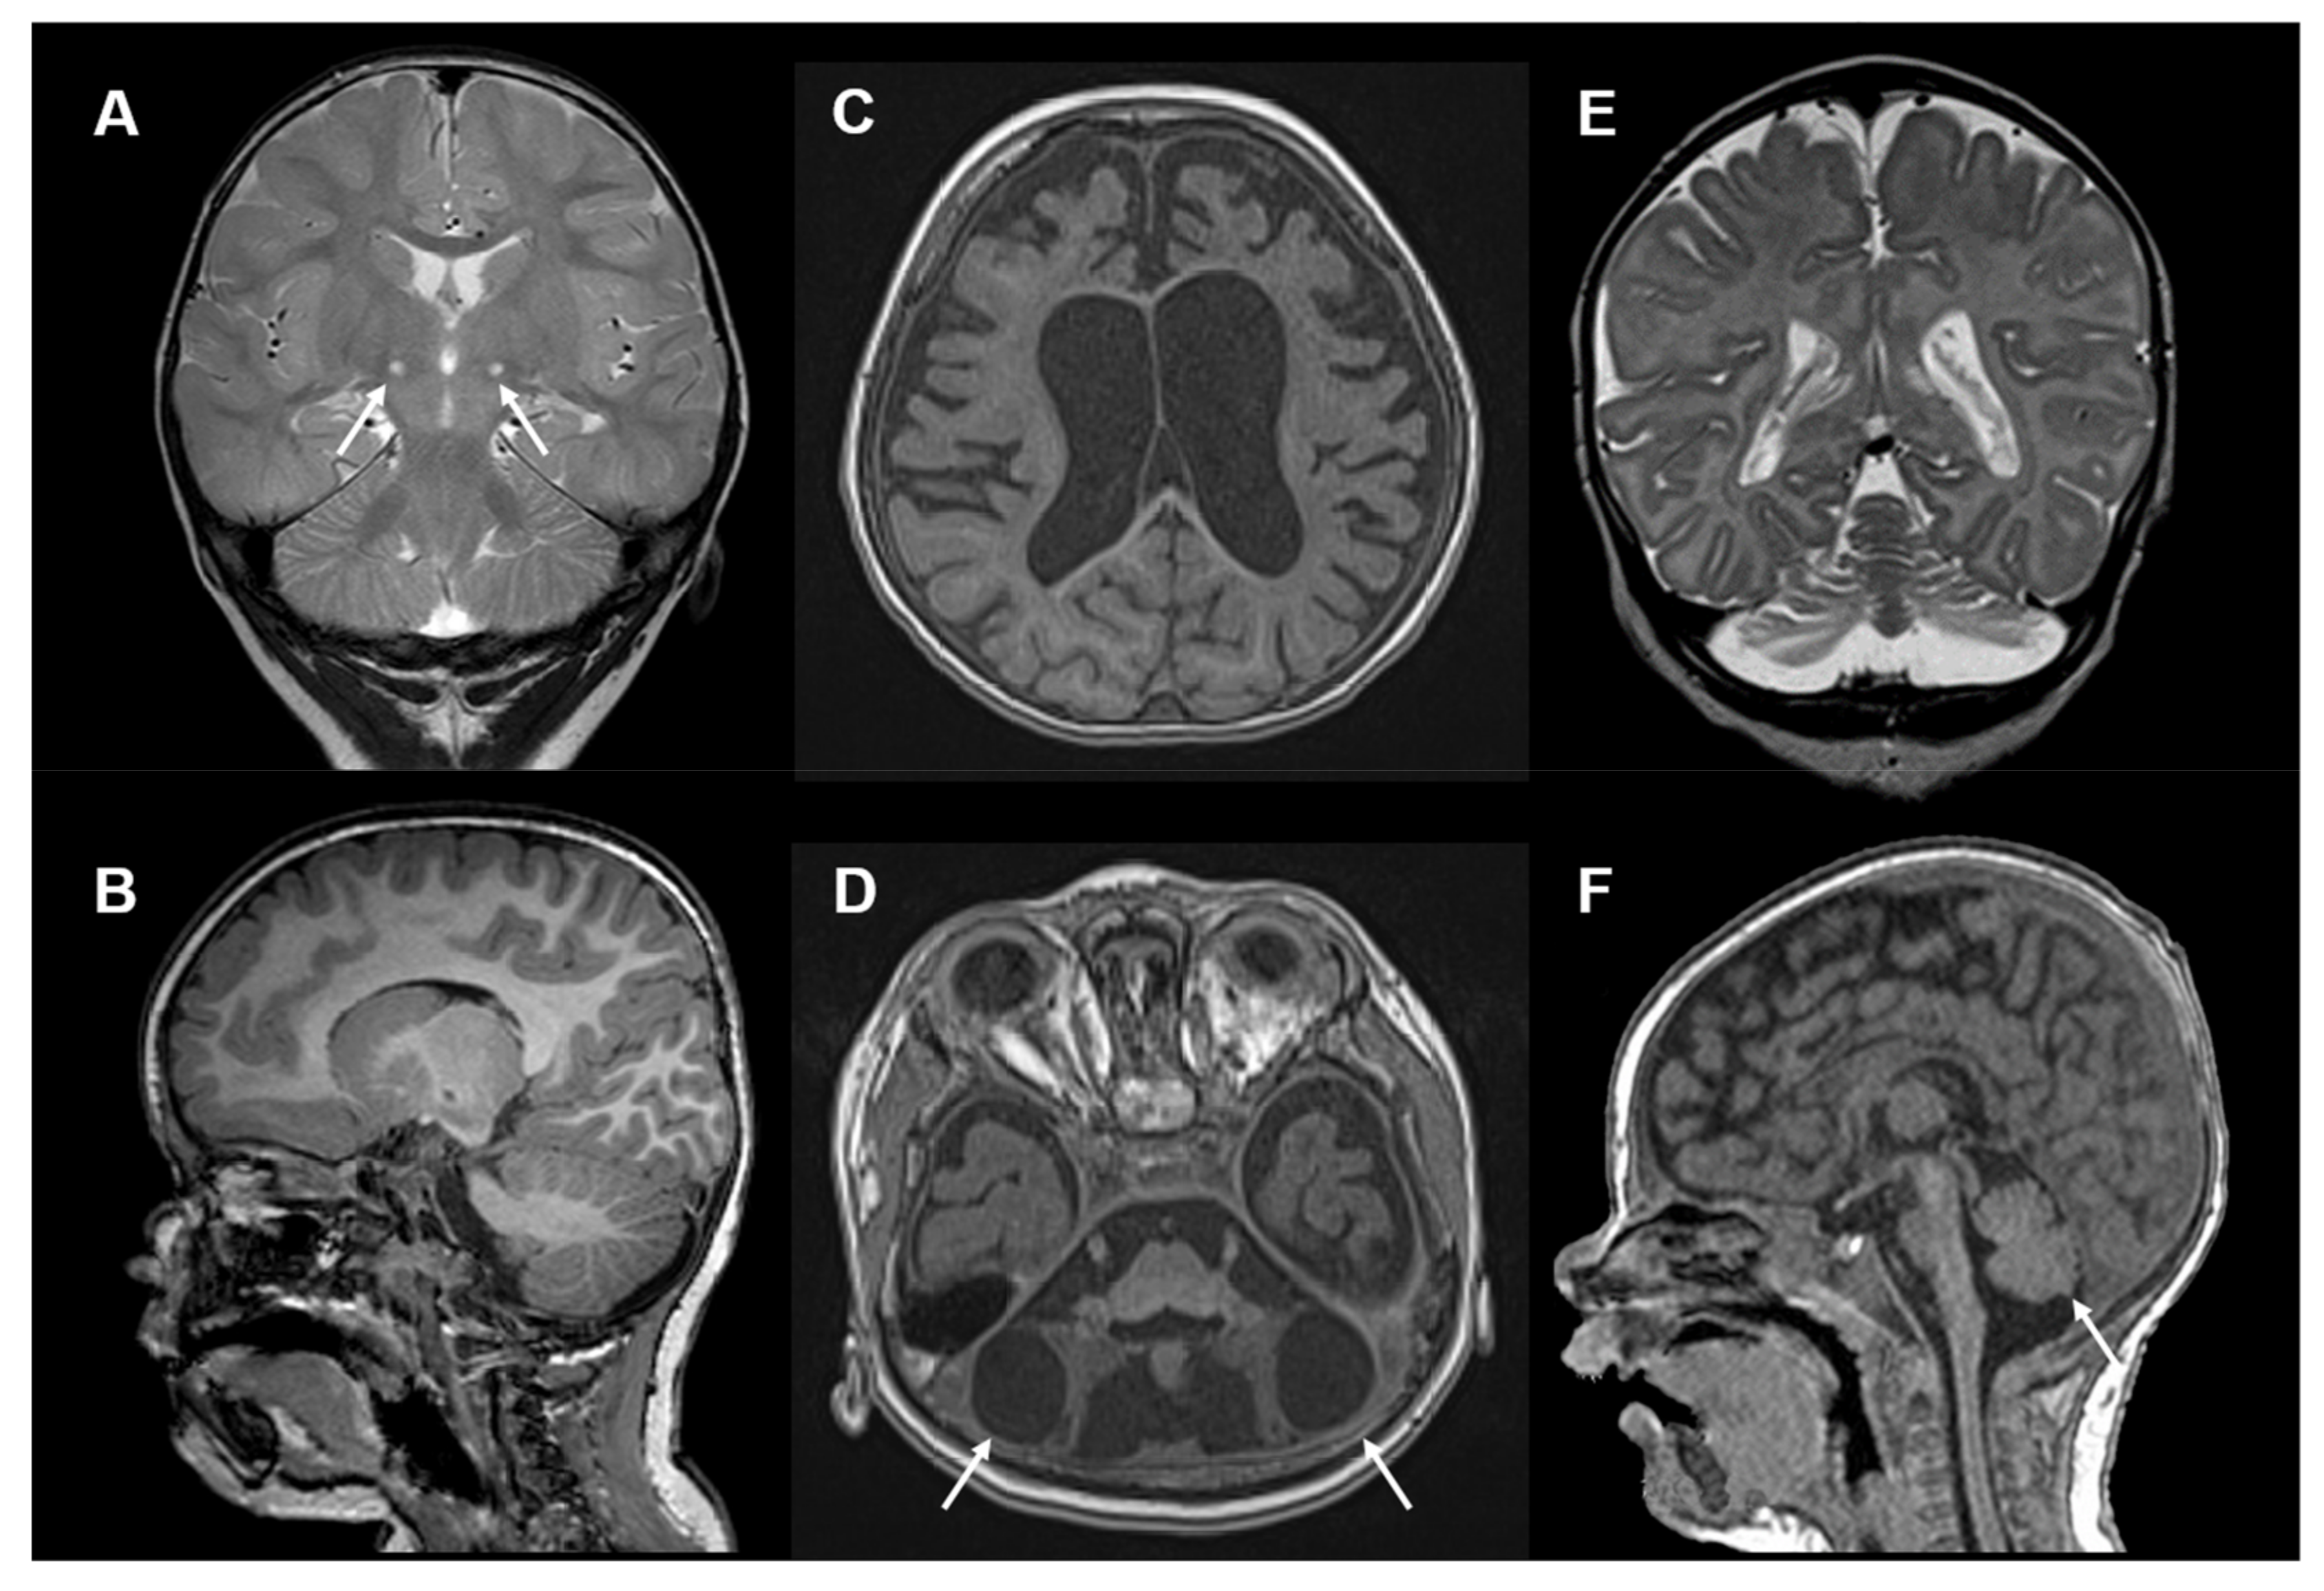

Examples of brain MRI imaging findings in COQ4 deficiency are depicted in Figure 3.

Figure 3.

Neuroimaging in COQ4 deficiency: (A) Brain MRI, T2-weighted, coronal images of a 15-month-old girl with COQ4 deficiency. Images show bilateral circumscribed lesions in the subthalamic nuclei (white arrows). (B) Sagittal T1-weithed MRI images show no cerebellar lesions. (C) Brain MRI, T1-weighted, axial images of an 18-month-old girl with COQ4 deficiency showing global brain atrophy. (D) Brain MRI, T1-weighted, axial images of the same child showing cerebellar degeneration with bilateral large cysts within the cerebellar hemispheres (white arrows). (E,F) T2-weighted, coronal and sagittal images and of a 2-month-old girl with COQ4 deficiency showing cerebellar hypoplasia (white arrow). Other MRI images of these individuals were published previously [30].

The most frequent finding was global cerebral atrophy. In addition, cerebellar abnormalities were found in the majority of cases. Cerebellar pathology included cases with hypoplasia (detected on pre- and early postnatal imaging) as well as cases with progressive atrophy. Another frequent abnormality was delayed myelination, which was seen in about half of the individuals. A unique/specific finding appeared to be a cystic malformation/degeneration of the cerebellum, which was observed in some of the individuals with severe and early disease onset. Another imaging finding in a subset of COQ4 patients were occipito-pariental stroke-like lesions. Apart from this MELAS-like pattern, individuals with a Leigh-like MRI pattern were also identified.

Based on the analysis of brain MRIs in COQ4 patients, a phenotypic classification with three subtypes was proposed: Type 1: cerebral atrophy and a mixture of cerebellar atrophy and hypoplasia. Affected individuals showed a severe clinical phenotype. Type 2: stroke-like lesions and mild global brain atrophy. Patients presented with an intermediate clinical phenotype. Type 3: nonspecific changes with mild, generalized brain atrophy, slightly delayed myelination and, in some cases, even normal brain MRI. Affected individuals showed a late-onset phenotype.